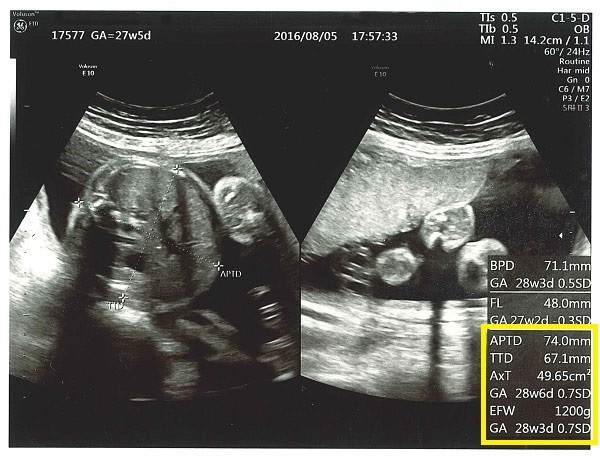

妊娠中期の超音波画像~その2~

これは別の妊娠中期の超音波画像です。黄色い四角の中の「APTD」は腹部前後径(ふくぶぜんごけい)で、赤ちゃんのおなかの前後の長さ、「TTD」は腹部横径(ふくぶおうけい)で、赤ちゃんのおなかの横幅の値です。

「EFW」は赤ちゃんの推定体重(estimated fetal weight)。推定体重はBPD、FL、APTD、TTDの数値から算出しています。あくまでも「推定」なので誤差も多少あるようです。これら以外にも、「AC」赤ちゃんのおなか周りの長さ、「AFI」羊水インデックス(羊水量を評価したもの)などがあります。